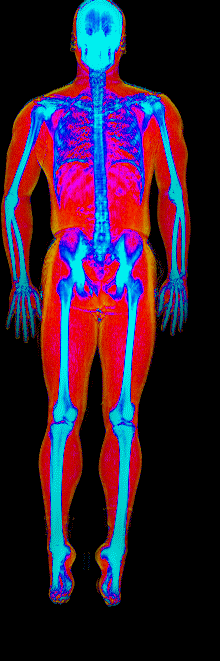

This page features real, anonymized DEXA scan images from BodyStats clients, organized by gender and body fat percentage in 5% increments. DEXA (Dual-Energy X-ray Absorptiometry) is the clinical gold standard for measuring body composition — far more accurate than scales, calipers, or visual estimates.

Each colorized scan shows the distribution of fat tissue (shown in warmer colors) and lean tissue (cooler colors) throughout the body. Compare your own DEXA scan to others in your range, or see what different body fat levels actually look like on a scan.

Male DEXA Scans by Body Fat %

10 to 15% body fat

15 to 20% body fat